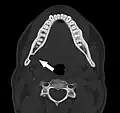

Stafne bone cavity seen on coronal CT -

Stafne bone cavity seen on axial CT

Stafne's defect is usually discovered by chance during routine dental radiography.[11] Radiographically, it is a well-circumscribed, monolocular, round, radiolucent defect, 1–3 cm in size, usually between the inferior alveolar nerve (IAN) and the inferior border of the posterior mandible between the molars and the angle of the jaw. It is one of the few radiolucent lesions that can occur below the IAN. The border is well corticated and it will have no effect on the surrounding structures. Computed tomography (CT) will show a shallow defect through the medial cortex of the mandible with a corticated rim and no soft tissue abnormalities, with the exception of a portion of the submandibular gland. Neoplasms, such as metastatic squamous cell carcinoma to the submandibular lymph nodes or a salivary gland tumour, could create a similar appearance but rarely have such well defined borders and can usually be palpated in the floor of the mouth or submandibular triangle of the neck as a hard mass. CT and clinical exam is typically sufficient to distinguish between this and a Stafne defect. The Stafne defect also tends to not increase in size or change in radiographic appearance over time (hence the term "static bone cyst"), and this can be used to help confirm the diagnosis.[11] Tissue biopsy is not usually indicated, but if carried out, the histopathologic appearance is usually normal salivary gland tissue. Sometimes attempted biopsy of Stafne defects reveals an empty cavity (possibly because the gland was displaced at the time of biopsy), or other contents such as blood vessels, fat, lymphoid or connective tissues. Defects of the anterior lingual mandible may require biopsy for correct diagnosis at this unusual location.[5] The radiolucent defect here may be superimposed on the lower anterior teeth and be mistaken for an odontogenic lesion. Sometimes the defect may interrupt the contour of the lower border of the mandible, and may be palpable. Sialography may be sometimes used to help demonstrate the salivary gland tissue within the bone.